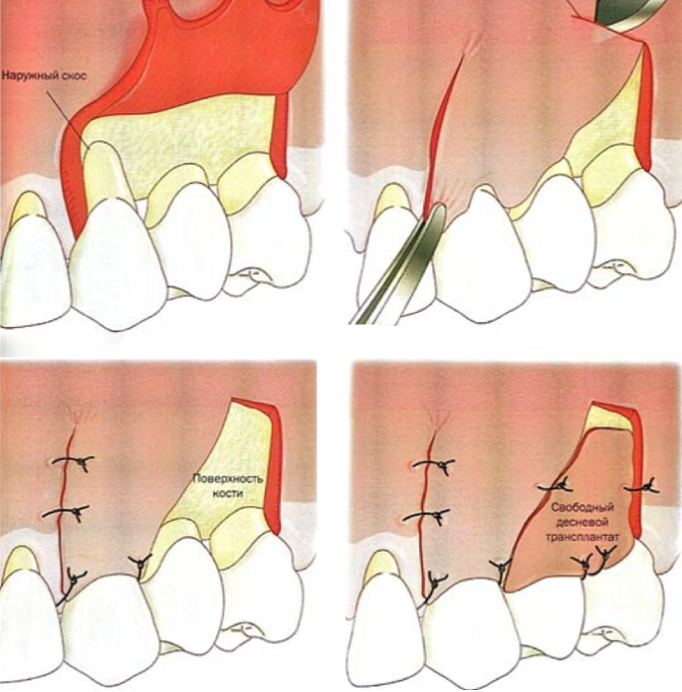

Методы

Метод восстановления мягких тканей определяется врачом с учетом всех факторов. В восстановлении могут использоваться:

Самый передовой и эффективный способ восстановления - использование мембран. Здесь не требуется забор тканей у пациента или донора. Мембраны гарантируют предсказуемый результат операции.

Этапы

Процесс восстановления объема занимает не более часа при использовании мембран. Этапы процедуры: